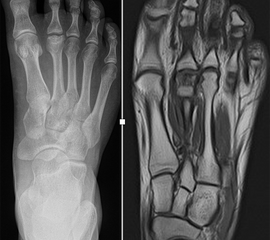

In der Regel bestehen aktive Wachstumsfugen bei Mädchen bis zum 12. und bei Jungen bis zum 14. Lebensjahr, mit Abweichungen von einem Jahr nach unten und nach oben. Präzise Informationen unter anderem darüber gibt das präoperative Röntgenbild (Abb. 2).

Abb. 2 a-c: offene Wachstumsfugen MT I Basis und Zehen (a), teilweise geöffnete Wachstumsfugen (b) und geschlossene Wachstumsfugen (c).

Die erforderlichen Osteotomien sind daher dem Fugenverlauf anzupassen, diese sind unbedingt zu respektieren. Wird eine Wachstumsfuge versehentlich mit der Fräse verletzt, kann durch partiellen oder kompletten Fugenverschluss ein Fehlwachstum provoziert werden. Achsabweichungen oder ein Wachstumstopp der betroffenen Region können die Folge sein. Offene Wachstumsfugen begrenzen die Osteotomieausrichtung besonders im Bereich des dorsalen Calcaneus, der Metatarsale I Basis und der IV. oder V. Zehe im End- und Mittelglied.